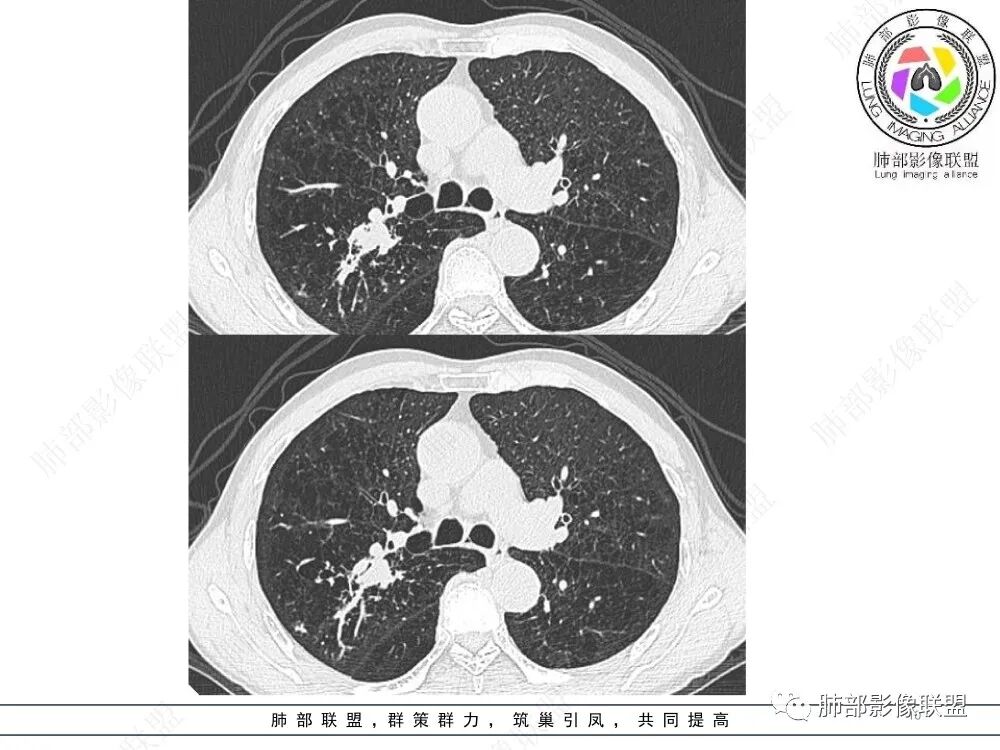

3、影像表现:肺气肿背景,右肺上叶后段支气管开口阻塞并见腔内软组织影轻度突向叶支气管,阻塞段以远支气管及分支扩张填塞呈指套样改变,轻度不均匀强化,外周点片影,符合阻塞性炎性表现,现有图像资料未见明确肺门纵膈淋巴结增大。

①鳞癌:老年男性,长期吸烟史,支气管腔内占位有强化、指套征,周围阻塞性炎症,常规需要考虑。

②小细胞肺癌:多见于吸烟男性,周围型多见,病灶沿支气管匍行,管壁增厚,阻塞有时不彻底,典型者呈鸭蹼和腊肠样凸起,增强沼泽样强化,阻塞性肺炎相对较轻,较少肺不张。易较早转移到纵隔和肺门淋巴结,出现“娘小崽大”特征,多个淋巴结融合则呈现“冰冻纵隔”。本例病灶有类似鸭蹼样改变,加上患者长期吸烟史、NSE增高,不除外小细胞肺癌,但纵隔及肺门淋巴结肿大、融合的趋势不明显。

上图,鳞癌,腔内软组织占位,局部膨大,不均匀强化,伴远端粘液栓。

上图,小细胞肺癌,病灶从肺门朝外沿支气管爬行,呈指套样改变,病灶周围阻塞性肺炎较轻。